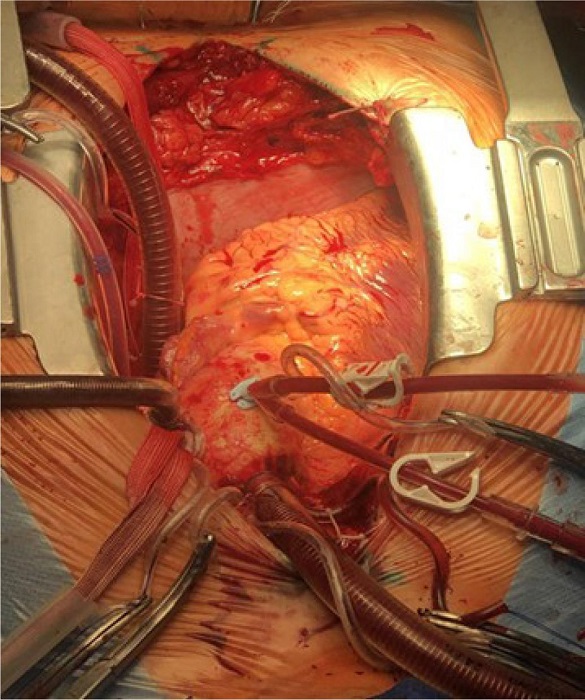

The patient underwent posterior mitral valve leaflet repair and mitral valve annuloplasty under CPB and antegrade cold cardioplegia. The surgical access was gained typically via median sternotomy. The special technical feature was that the aorta and great vessels in the wound were mirrored from the normal position. Purse string sutures for cannulation of the aorta and vena cava were technically placed in a standard manner, but the placement itself was in the left parts of the surgical wound, i.e., “non-standard” (Figure 5).

Access to the mitral valve was obtained through atriotomy performed on the left flank of the surgical wound. After the mitral valve revision and identification of changes (the fibrous ring was not dilated, the posterior leaflet of the mitral valve was thickened, the ruptured chord was at P3 segment), posterior mitral valve leaflet repair was performed. A support C-Ring was inserted in mitral position. An intraoperative transesophageal echocardiography confirmed that mitral regurgitation was not observed.